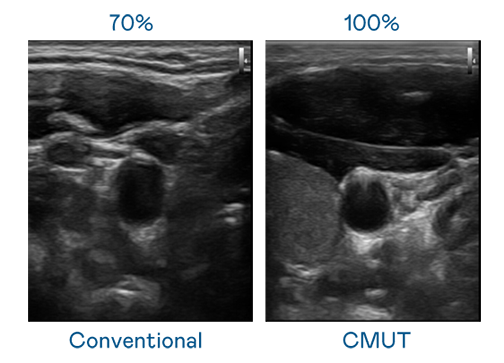

CMUT 技术是一种用电容式微机电元件来产生超音波讯号的技术。与传统 PZT 压电式技术相比,CMUT 频宽增加 30%,更宽频的超音波讯号让影像解析度大幅提升,是实现高影像品质医疗超音波扫描、促进精准医疗发展的关键技术。

大频宽带来超清晰影像

超音波影像的解析度高低,首先取决于探头能发出的讯号频宽。AG百家乐试玩 CMUT 可提供高清晰的超音波讯号,提供高频宽、高灵敏度、影像纹理细节更高的超音波影像,协助医护人员缩短影像判读时间及利用精准的医疗影像进行诊断。